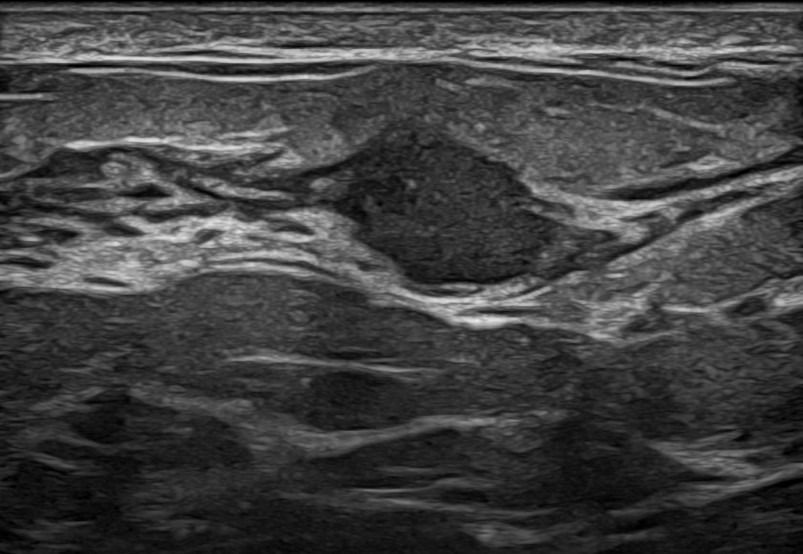

Modern ultrasound machines, equipped with advanced high-frequency transducers, techniques such as Color Doppler, Power Doppler, B-Flow, and Elastography, allow the analysis of breast architecture with exceptional accuracy.

Elastography can highlight the elasticity of a lesion, indicating whether it is hard or soft. Through this technique, we can assess the nature of the lesion, providing indications of whether it is benign or malignant. Additionally, with the contribution of Color Power Doppler and B-Flow, we can monitor the vascular flow within the lesions, offering even more information about the type and nature of the abnormality.